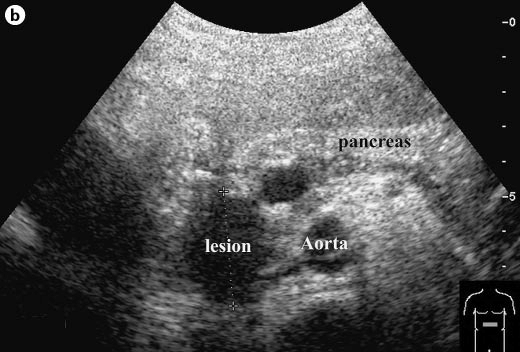

Sonographic appearance of the adult pancreas

Anatomical relationships:

-IVC

Posterior to head

Anatomical relationships

-Duodenum

Lateral to head

Anatomical relationships

-Portal confluence (or SMV)

Medial to head/ anterior to uncinate process/ posterior to neck

Anatomical relationships

-Splenic vein

Posterior to body/tail

Anatomical relationships

-Splenic artery

Superior to body/tail

Anatomical relationships

-SMA

Anterior to aorta/ posterior to pancreas body and splenic vein

Anatomical relationships

-left renal vein

Posterior to SMA

Anterior to aorta

Anatomical relationships

-right renal artery

Posterior to IVC